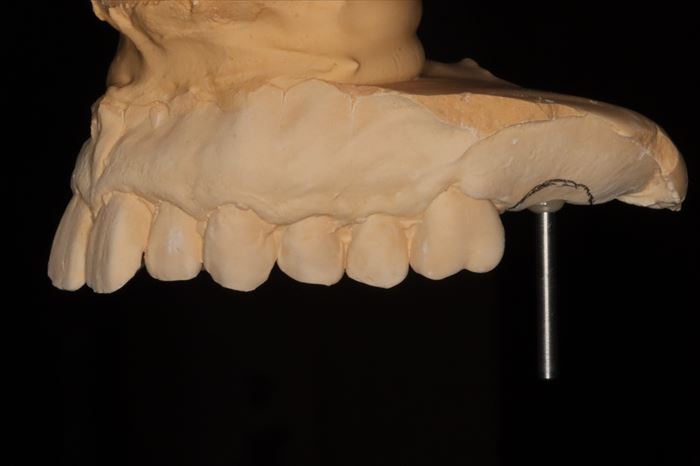

フェイスボウトランスファーの記録を利用してKaVo プロター evo7 咬合器に上下歯列石膏模型をマウントしました。

インプラントを埋入する部位を石膏模型上で確認します。

位置・角度をシミュレーションします。

サージカルステント(ドリルガイド)を作成してインプラント埋入オペに臨みます。